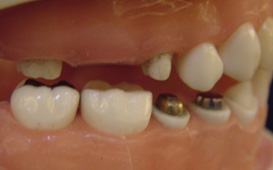

單顆雙植體 案例一

缺一顆牙時,製作牙橋或放置一單顆植體的差別 缺牙的處理,一般有兩種方式,一是製作牙橋,另一是放置人工植牙。 牙橋的好處是製作時間快,費用可能較節省 ( 因為材質不同而有不同 ),費用大約在兩三萬附近,若含黃金比例高有可能高達6 - 7萬元 ; 但是缺點就是要修磨旁邊的牙齒,比較可惜,而且一旦是假牙,就終身是假牙,而重建的咬合也較差 ( 兩人做三人的工作 ) ,因為仍舊是少一個牙根,不過仍比不做好。 放人工牙根,也就是植牙,其最大好處就是不用修磨旁邊的牙齒,這一點其實是無價,而且完成後的咬合功能很好,幾乎和自然牙一樣,但植牙的費用較牙橋高,一顆植牙費用大約是六萬多塊到八九萬塊,會因為使用廠牌和有沒有補骨頭而有費用高低之不同,但植牙的使用年限較長,同時可避免周圍的骨頭繼續減少 ; 若照顧良好,也可能好幾十年,一般而言,十年的成功率有百分之八九十,算是非常高 ; 植牙因為要等骨頭和植體長牢,所以需要一些時間,一般上顎的牙要五、六個月,下顎因骨頭較為緻密,所以只需三四個月,但以長期的健康考慮,幾個月其實很快;以專業的建議,植牙確實比較好。

植體設計